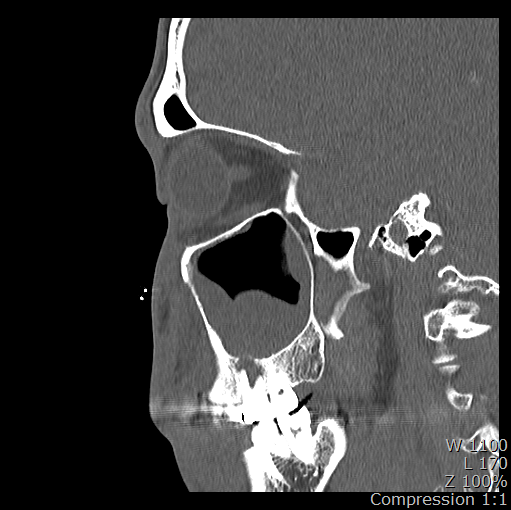

5/31 : 녹색 콧물 나오는 증상으로 이비인후과 방문 후 부비동 CT검사

6/5 : 검사 판독 후 부비동염은 치과적 원인으로 보이며, 16번 치아는 크라운 아래로 다 썪어 휑하게 뚤렸을 것 같다며 구강외과 협진의뢰.

3. 파노라마나 CT를 보면 16번 치아 뿌리쪽과 부비동쪽 둥그런 구조물 사이가 검게 음영이 생겨 있는데 이게 구조물의 영구적 손상이 있는 걸까요? 아니면 치료 후에 다시 회복되는 걸까요?

23년 5월 부비동CT

-저부위는 염증때문에 펴가 녹아서 나타나는 부분으로 발치후 어느정도 기다리면 뼈가 차긴찹니다.